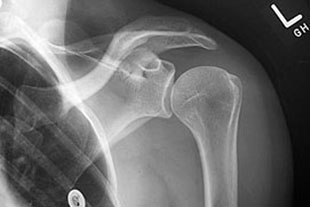

Die Erstdiagnostik bei akuten Schulterschmerzen besteht in der Sonographie (Ultraschalluntersuchung) und einer Röntgenuntersuchung. Hierbei kann bereits sehr genau auf die Ursache der Schmerzsymptomatik geschlossen werden. Sowohl die Rotatorenmanschette (= Muskel-Sehnen-Kappe der Schulter) als auch das Schulterdach und eventuell entzündete Schleimbeutelveränderungen können sehr genau lokalisiert und in der Ausdehnung erkannt werden.

Möglicherweise vorhandene Kalkdepots kommen ebenfalls zur Darstellung. Speziell bei Schulterluxationen (Auskugeln des Schultergelenkes) und Schulterschmerzen nach einem Unfall empfiehlt sich die Durchführung einer kernspintomografischen Untersuchung (MRT), weil hierbei die Ausdehnung von Rotatorenmanschettenrissen oder eine eventuelle Gelenklippenverletzung genau dargestellt werden können.